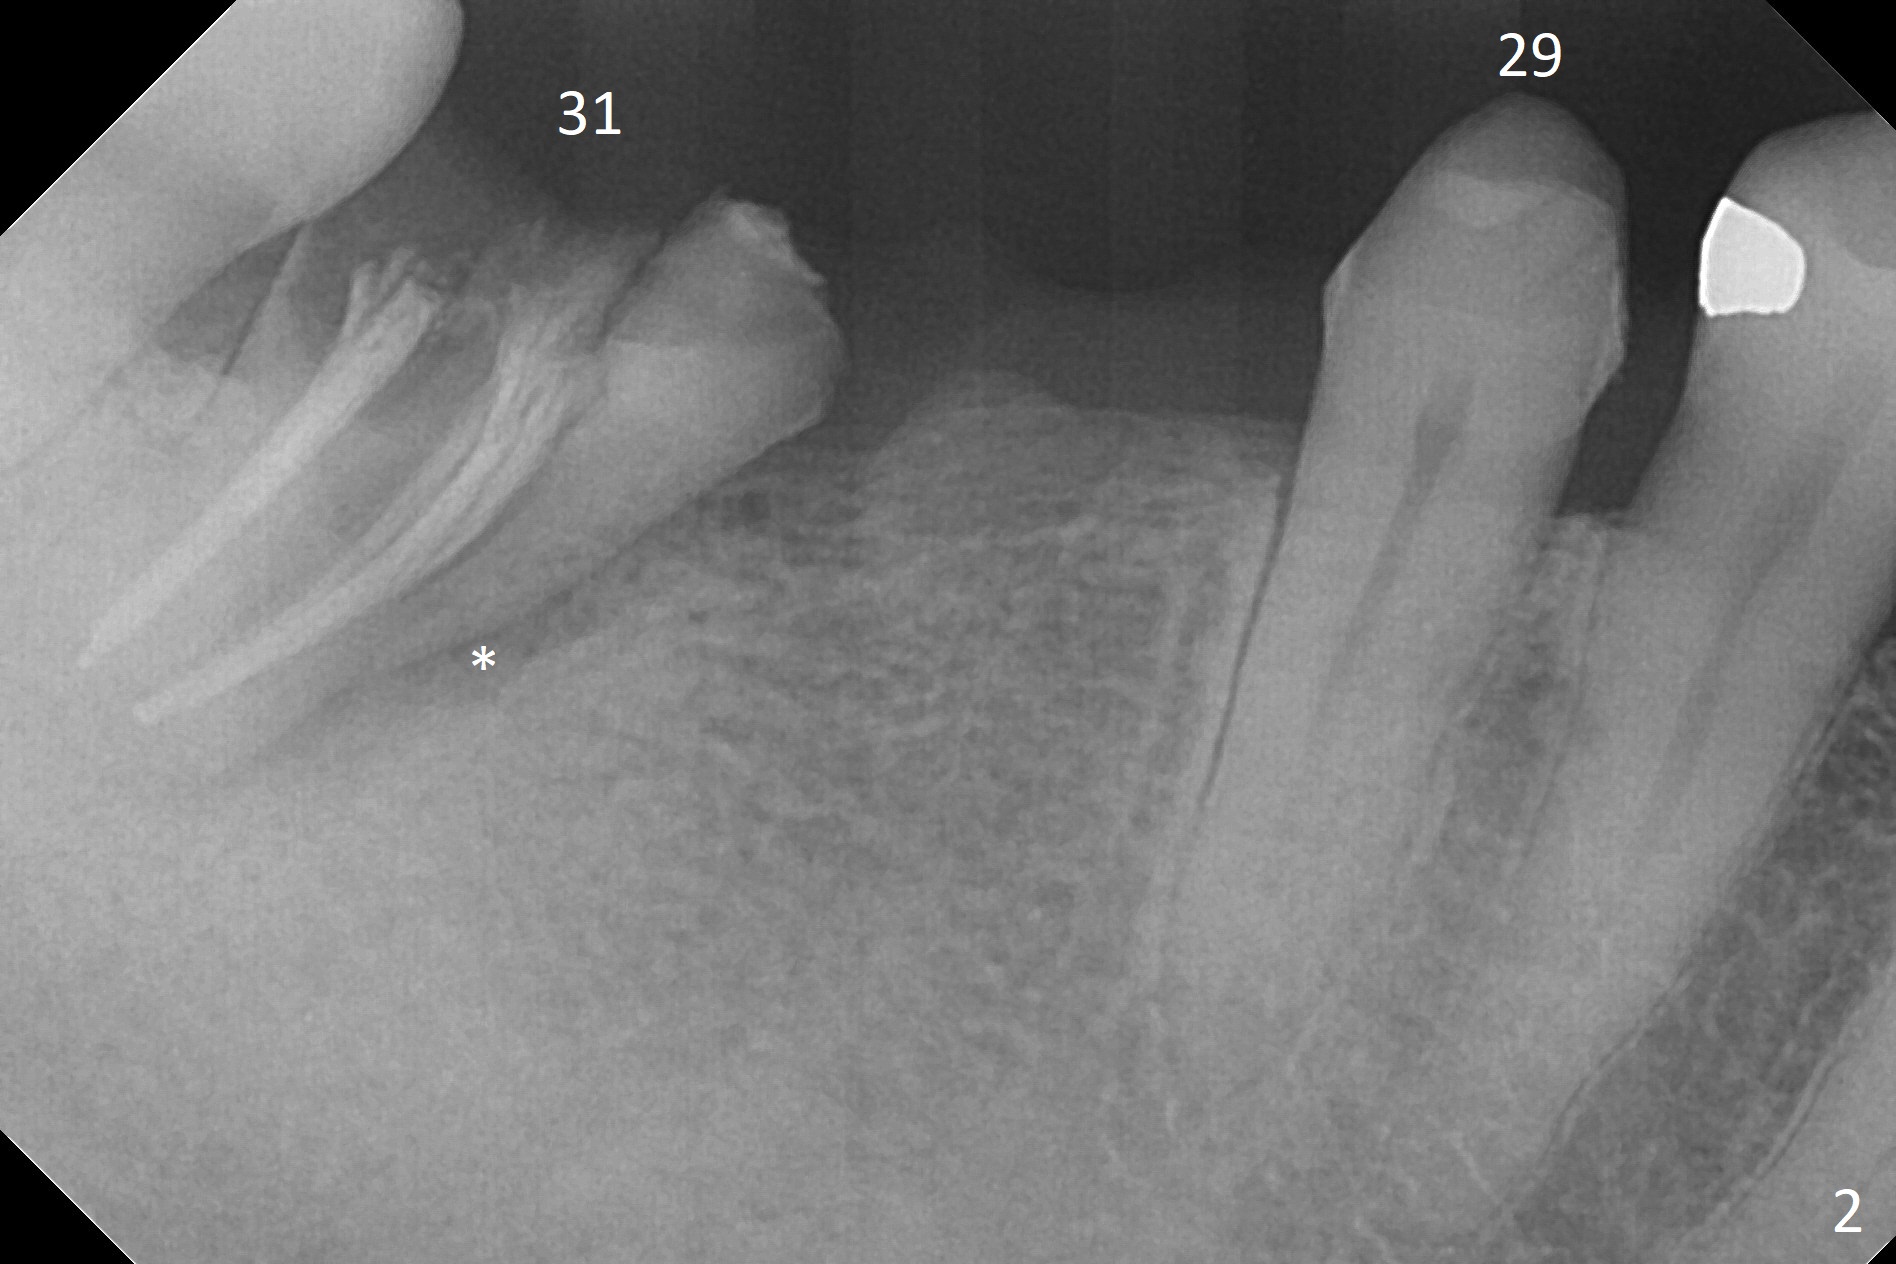

A 53-year-old woman has 2 lower failed FPDs with the right one dislodged (Fig.1,2). The pontic (#30) is as narrow as a premolar; prepare a 3.5 or 4.0 mm 2-piece implant (Fig.3). To gain more native bone for primary stability at #31, use Point Lindamann drill to initiate osteotomy in the middle of the mesial slope obliquely (Fig.4) and change trajectory (Fig.5). Sequential osteotomy may distalize the final position of the osteotomy to the planned one (as compared to Fig.3) because of the slope. The patient has been instructed to use water pik to reduce the erythema at the pontic before surgery. Take photos to demonstrate the point. Surgical stent is finished.